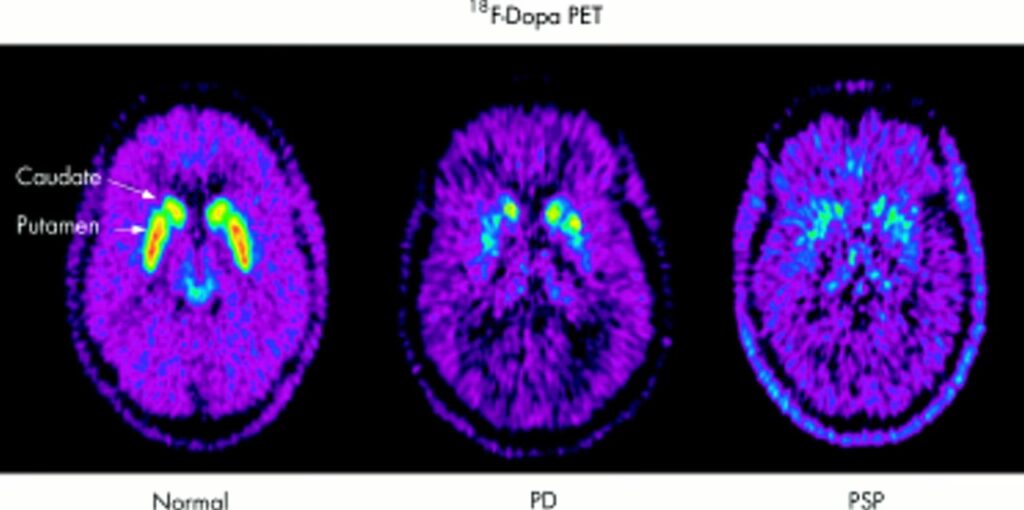

- Trastornos del Movimiento: La PET puede ser útil en la evaluación de trastornos como la enfermedad de Parkinson, visualizando la función de los sistemas de neurotransmisores dopaminérgicos.